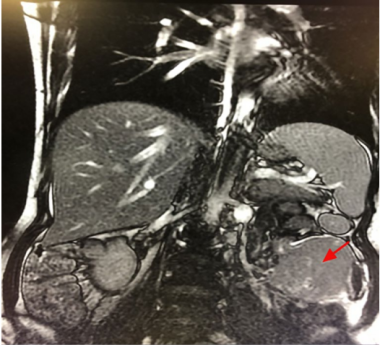

B超显示肝内多发低回声结节。最大的在左肝,大约3.4cm× 2.5cm,右肝约5.7cm× 5.2cm。两处边界清晰规则,内部可见血流迹象。MRI检查提示肝脏内有多个肿块,有转移的可能。在左下腹发现一个肿块,很有可能是恶性(图1)。

图1